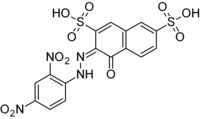

| IUPAC name

(3E)-3-[(2,4-Dinitrophenyl)hydrazono]-4-oxonaphthalene-2,7-disulfonic acid | |

| C16H10N4O11S2 | |